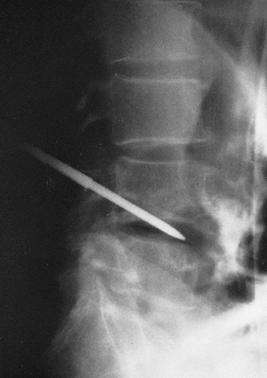

Figure 150.1.

Hematogenous osteomyelitis most commonly invades first the anterior portion of the vertebral body, just adjacent to the endplate. Radiographic changes take time to appear and the usual picture is that of simultaneous involvement of two adjacent endplates with narrowing of the intervertebral disc space. This tomogram of the lumbar spine shows endplate destruction of the lower vertebral combine with loss of a good deal of the body of the upper vertebra. |